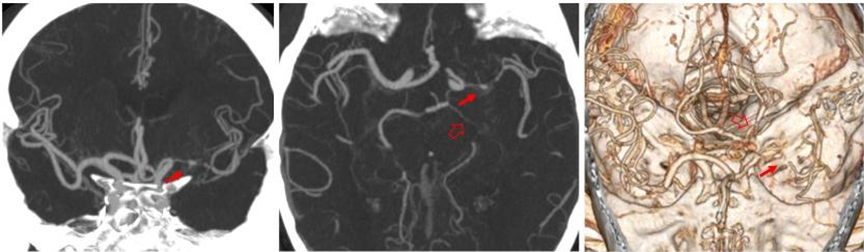

左侧大脑中动脉重度狭窄(红箭),左侧大脑后动脉重度狭窄(空心箭)。